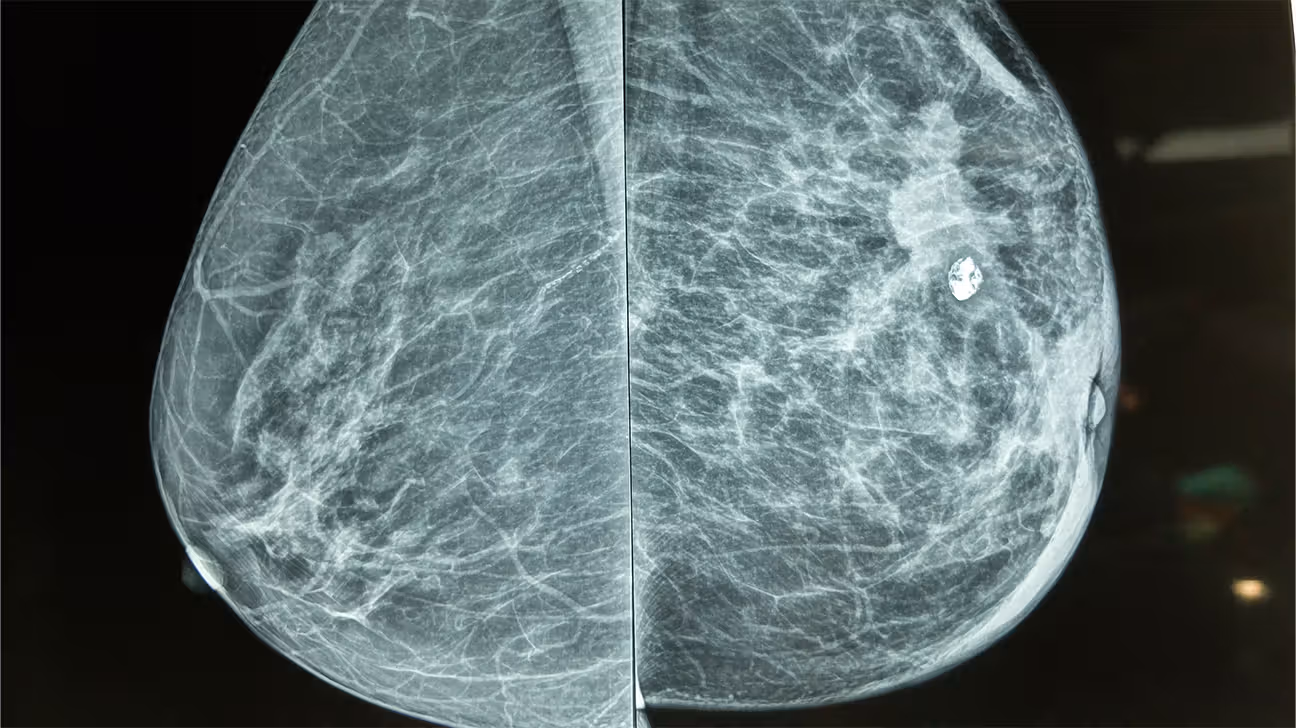

The most significant and widely discussed factor is the physical barrier the implant creates between the X-ray source and the detector. Because both silicone and saline implants are substantially denser than natural glandular and fatty breast tissue, they absorb a greater amount of the X-ray energy, resulting in the aforementioned white shadow. This shadowing effect is not trivial; depending on the size and placement of the implant, studies have estimated that between 20% to over 80% of the natural breast tissue, particularly the posterior aspects near the chest wall, can be visually obscured on standard mammographic projections. Without specialized positioning, this reduced visibility creates an area of concern, as a small, developing tumor within the shadowed zone could be missed. This underscores the necessity of a tailored procedure rather than a generic screening protocol.

To counteract the implant’s obscuring effect, a specialized technique known as the Eklund view, or implant displacement view (ID), was introduced and has since become the globally recognized standard of care. This technique involves a skilled mammography technologist using gentle, focused pressure to push the implant posteriorly, toward the chest wall, while pulling the natural breast tissue forward and away from the implant. The separated tissue is then compressed and imaged independently, allowing for a much clearer visualization of the anterior and central breast parenchyma without the dense implant shadow overlay. This maneuver effectively doubles the number of images taken during a typical screening—from four standard views to eight (four standard views plus four ID views)—and is crucial for maximizing the amount of visible glandular tissue for radiological assessment. Crucially, the proper execution of the Eklund technique compresses only the breast tissue, not the implant itself, making the risk of implant rupture during the procedure exceedingly low, especially with modern, cohesive gel devices.

Beyond the visibility issue, there is the concurrent need to assess the integrity of the implant itself during the screening process. While mammography is the gold standard for breast tissue evaluation, it is not the most sensitive tool for detecting subtle or contained implant ruptures, particularly in the case of silicone implants. Saline implants, when ruptured, are typically obvious due to the rapid deflation of the shell, but a slow, intracapsular rupture of a silicone implant (where the silicone remains contained by the fibrous capsule) can be “silent” and missed on mammography because the dense silicone gel simply continues to cast a uniform shadow. For this specific concern, supplementary imaging, such as a dedicated breast ultrasound or, more definitively, a magnetic resonance imaging (MRI) scan, is often recommended, especially for women with silicone implants or those experiencing symptoms like changes in breast contour or hardness.